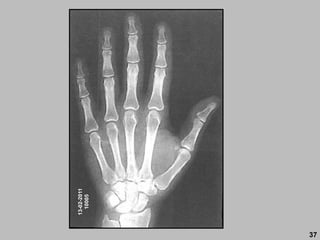

13-02-2011

10005

DIREITO

BONTRAGER

27

PRÁTICA

28

ROBERTO

PACIENTES

INTERNADOS

29

30

ESQUERDO

31

32

33

34

ESQUERDA

35

DIREITA

36

37